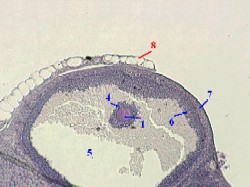

| Морфоло- гия: размеры, полость | I. Размер ооцита (6Б) в третичных фолликулах – таков же, как во вторичных, т.е. рост ооцита прекращается на стадии вторичного фолликула. II. Сами же третичные фолликулы – наиболее крупные среди всех фолликулов яичника и обычно находятся у поверхности яичника, сильно её выпячивая. III. а) Основной объём фолликула занят большой полостью с жидкостью (6А). б) Могут присутствовать также малые полости, | Рисунок с препарата - граафов пузырёк в яичнике. Окраска гематоксилин- эозином. Полный размер |

окружённые розеткообразными скоплениями фолликулярных клеток и ещё не успевшие слиться с основной полостью. | ||

| Связь ооцита со стенкой фолликула | IV. а) Долгое время ооцит вместе со своими оболочками сохраняет связь со стенкой фолликула, образуя в ней т.н. яйценосный бугорок (6Е). б) Таким образом, ооцит располагается на периферии фолликула | |

(тогда как в примордиальных и первичных фолликулах он занимает центральное положение). в) Непосредственно же перед овуляцией указанная связь со стенкой теряется, и ооцит (с оболочками) начинает свободно плавать в фолликулярной жидкости. |

| Виды оболочек | Рассматривая третичный фолликул, выпячивающий поверхность яичника, надо различать оболочки трёх уровней, а именно оболочки ооцита, фолликула и яичника в целом. | |

| 1. Оболочки ооцита | а) Оболочки ооцита (1) – это блестящая (2) и зернистая (4) оболочки, где последняя образована частью фолликулярных клеток, лежащих в один или несколько слоёв. б) Сделаем по поводу данных оболочек два замечания. | 2,б-в. Препарат - яичник. Окраска по Маллори. в)Большое увеличение Полный размер |

| Другие структуры | Завершая рассмотрение этого снимка, укажем, что на нём отмечены цифрами также полость (5) фолликула, заполненная жидкостью, и текальная оболочка (7). | |

| 2-3. Оболочки фолликула и яичника | Обратимся к оболочкам двух следующих уровней. а) Оболочки фолликула - это пристеночный слой фолликулярного эпителия (6), и двуслойная тека (7). б) А оболочки яичника (8) – | б)Малое увеличение Полный размер |

белочная оболочка и мезотелий. Именно эти оболочки – фолликула и яичника – должны разорваться при овуляции. | ||

| Замечание по препарату | На приведённом снимке уже не видно связи ооцита (1), окружённого оболочками (4), со стенкой фолликула. Это обусловлено либо тем, что ещё существующая ножка яйценосного бугорка не попала в срез, | |

либо тем, что эта ножка уже разорвалась и ооцит (с оболочками) свободно плавает в жидкости, заполняющей полость (5) фолликула. |